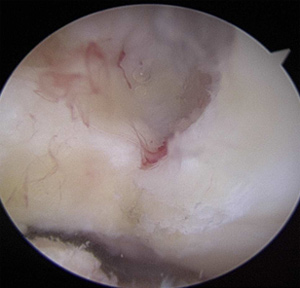

Pictures 9-10 show the graft in place and fixated with a screw. The last picture shows the new graft remaining taut as it is pulled on by a surgical prob.